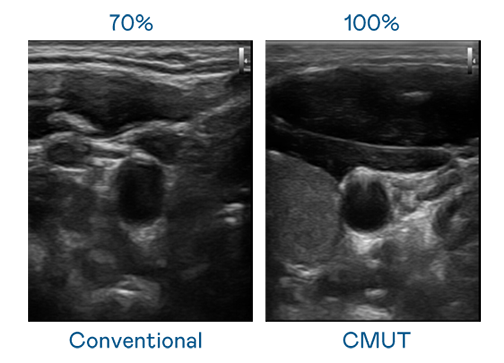

CMUT 技术是一种用电容式微机电元件来产生超音波讯号的技术。与传统 PZT 压电式技术相比,CMUT 频宽增加 30%,更宽频的超音波讯号让影像解析度大幅提升,是实现高影像品质医疗超音波扫描、促进精准医疗发展的关键技术。

超音波影像的解析度高低,首先取决于探头能发出的讯号频宽。富易堂 CMUT 可提供高清晰的超音波讯号,提供高频宽、高灵敏度、影像纹理细节更高的超音波影像,协助医护人员缩短影像判读时间及利用精准的医疗影像进行诊断。